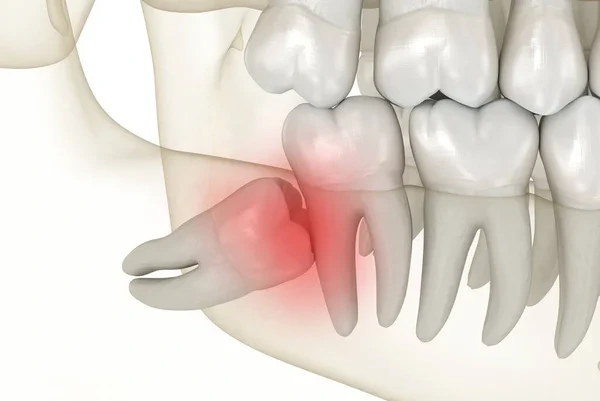

Wisdom teeth extraction in Beirut is a safe and painless procedure used to remove impacted or problematic third molars that can cause pain, infection, swelling, or pressure on nearby teeth.

At our clinic, each case is carefully evaluated using advanced imaging such as CBCT when needed, especially for lower wisdom teeth near the nerve, ensuring maximum safety. Whether the tooth is fully erupted or impacted, the procedure is performed with a gentle and precise approach, allowing for fast recovery and minimal discomfort.

Early removal of wisdom teeth can prevent future complications and protect your overall oral health.